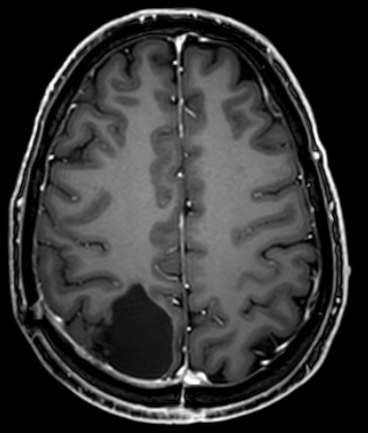

The MRI after 3 months, shown below, is encouraging. No relapse so far.

The treatment is not finished yet. There are 6 rounds of 1 full week of heavy chemo whereby he follows the protocol starting 1 week before and covering the week of the chemo. Throughout the rest of the period he remains close to very low carb but not fully.

We’ll have to wait for the next 5 years to see how successful we have been but in the mean time another scan was done, 6 months post surgery, with a doctor who was very enthusiastic about the result. Still nothing came back so far. Crossing fingers.